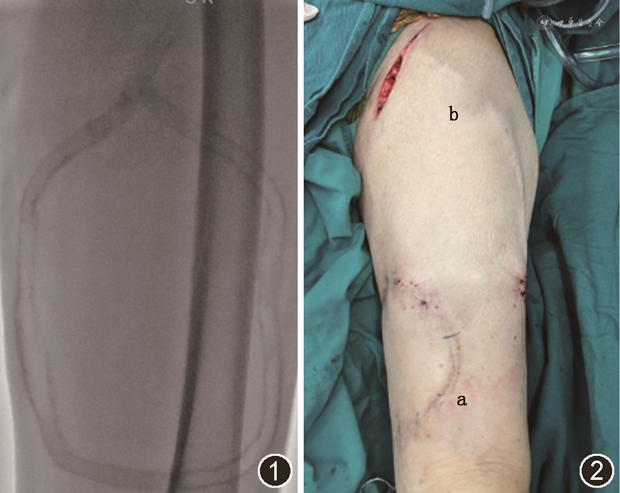

1. AVG狭窄和血栓发生情况:随访期间下肢AVG狭窄48例(62.3%),均存在静脉吻合口狭窄,合并人工血管穿刺点狭窄19例,髂静脉狭窄14例。人工血管穿刺点狭窄均行经皮球囊扩张成形术(percutaneous transluminal angioplasty,PTA),5例后期因整根人工血管钙化(图1)难以扩张及穿刺不便,于术后50~94个月弃用原AVG,于近心端(3例)(图2)或对侧(2例)下肢新建AVG。静脉吻合口狭窄闭塞病变4例行开放手术,2例间置人工血管至近心端股静脉,2例由原大隐静脉吻合口转位间置人工血管至股浅静脉。其余44例均行PTA治疗,其中22例于静脉吻合口处植入覆膜支架。髂静脉狭窄闭塞病变14例,2例病变与术前无明显改变且无症状未干预,1例髂静脉受压侧支开放经对侧髂静脉回流通畅未干预,11例于术后6~54个月植入裸支架,随访期间无支架内再狭窄,支架通畅时间(19±15)个月。合并血栓24例(31.2%),其中4例分别于术后2、3、6、19个月AVG血栓形成,因穿刺不便及交通不便自行弃用未处理,20例行切开取栓,其中1例取栓后造影通畅,余19例造影见狭窄,行介入治疗后通畅继续使用。平均干预次数0.73次/人年。